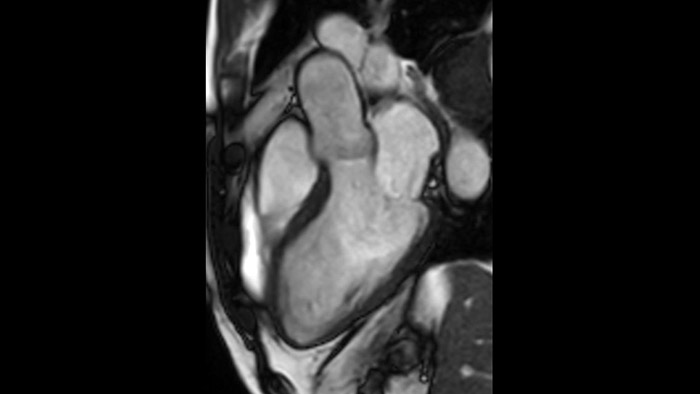

Diagnostic and prognostic utility of cardiac MR is increasing. Assess the anatomy and function of the heart using cine acquisitions, acquire information about perfusion and viability of the cardiac tissue, visualise potential edema with black blood sequence, access and even quantify tissue characterisation with CardiacQuant.

Addition of Compressed SENSE to your cardiac exams reduces the time spent in the MRI scanner for the patient and enables the reduction of breath hold times while maintaining virtually equal image quality4. Compressed SENSE is applicable to both 2D and 3D acquisitions.